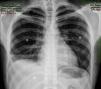

Presentamos el caso de un paciente varón de 21 años, fumador de un paquete/día, que acude a urgencias por referir dolor torácico súbito punzante en el lado derecho y disnea. A la exploración, consciente y orientado, y hemodinámicamente estable. La auscultación pulmonar objetiva un descenso del murmullo vesicular en la base de hemitórax derecho, sin evidenciar ingurgitación yugular. En la radiografía anteroposterior de tórax se aprecia un importante hidroneumotórax derecho con un colapso pulmonar moderado y un nivel hidroaéreo que llega a campo medio pulmonar derecho (fig. 1). Se inserta un tubo de drenaje torácico n.° 20 en hemitórax derecho a nivel del 5.° espacio intercostal en línea axilar anterior con drenaje de aire y menos de 100ml seroso no hemorrágico. Antes de ingresar en planta, se comprueba radiológicamente que el tubo está bien colocado y el pulmón derecho reexpande adecuadamente. A las 24h, el paciente refiere empeoramiento del estado general con abolición del murmullo vesicular en hemitórax derecho, una tensión arterial 90/60, drenaje de más de 800ml hemático y más de 400ml por hora hemático. Se realiza una TAC torácico con contraste intravenoso en el que se objetiva un neumotórax derecho con tubo de drenaje y un voluminoso nivel líquido (hemoneumotórax) que provoca atelectasia compresiva del lóbulo inferior derecho. La cavidad de neumotórax muestra un tracto compatible con bridas sin identificar el foco hemorrágico. Se completa el estudio con embolización arterial intercostal, y ante la sospecha de que el origen del sangrado sea las arterias intercostales que limitan el espacio intercostal por el que el tubo de drenaje entra a la cavidad torácica, se decide embolización de la parte distal de las mismas (fig. 2). El débito total es de 2.100ml hemático, y analíticamente presenta una hemoglobina de 8,6g/dl, precisando de transfusión sanguínea y reposición de la volemia. Durante su postoperatorio, el paciente evoluciona favorablemente, tanto desde el punto de vista radiológico como clínico, siendo retirado el tubo a los 10 días.